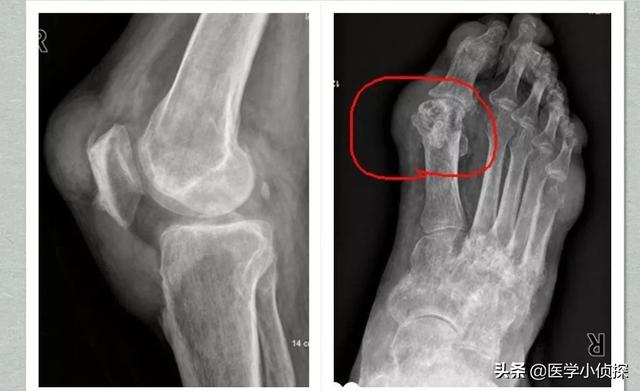

第2段階は、例えば超音波検査で「ダブルトラックサイン」を検出したり、画像検査を行うことである。デュアルエナジーCTで尿酸塩沈着が見つかるなど、そしてX線検査で軟部組織の腫脹、軟骨辺縁の破壊、関節面の不整が認められる。!

痛風は画像診断で発見することができ、関節軟骨の「ダブルトラックサイン」関節液貯留、骨びらんなどの有無、腎機能指標でも診断することができる。

- (10) 左右非対称の関節内腫脹(X線で確認)

- (11) 骨びらんを伴わない骨皮質下嚢胞(X線で確認)